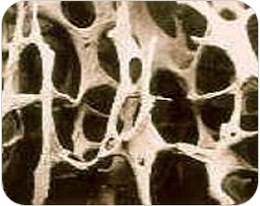

그런데 단단하고 치밀해야 할 우리 몸의 뼈가 양이 줄어들고 얇아져서 잘 부러지는 병이 있어. 마치 새의 뼈처럼 구멍이 숭숭 생기는 병인데, 이걸 '골다공증'(骨多孔症, '뼈에 구멍이 많은 증상'라는 뜻이야)이라고 해. 뼈의 주성분인 칼슘이 급격히 빠져나와서 정상 뼈에 비해 골밀도('뼈 안쪽이 가득 차 있는 정도'를 말해)가 낮아진 상태지. 골다공증에 걸리면 뼈가 잘 부러지기도 해서, 골다공증이 있는 환자는 정상인보다 뼈가 부러질 위험이 3배 높고, 골절로 인해 사망에 이를 확률이 8배 높단다.

정상 뼈(왼쪽)과 골다공증에 걸린 뼈(오른쪽)인데, 차이가 확 보이지? (출처=영등포보건소 건강정보, 골다공증)